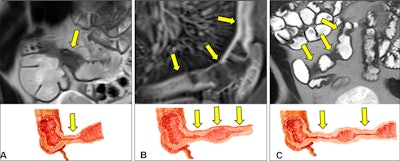

The Stenosis Therapy and Anti-Fibrotic Research (STAR) Consortium definition of a single stricture. (A) Coronal MR image and illustration show a single bowel segment with continuous luminal narrowing and bowel wall thickening (arrows). (B) Coronal MR image and illustration show multiple narrowed segments linked by imaging findings of inflammation, such as mesenteric border inflammation (arrows). (C) Coronal MR image and illustration show multiple narrowed segments (arrows) separated by 3 cm or less. Images and caption courtesy of the RSNA.The Stenosis Therapy and Anti-Fibrotic Research (STAR) Consortium definition of a single stricture. (A) Coronal MR image and illustration show a single bowel segment with continuous luminal narrowing and bowel wall thickening (arrows). (B) Coronal MR image and illustration show multiple narrowed segments linked by imaging findings of inflammation, such as mesenteric border inflammation (arrows). (C) Coronal MR image and illustration show multiple narrowed segments (arrows) separated by 3 cm or less. Images and caption courtesy of the RSNA.